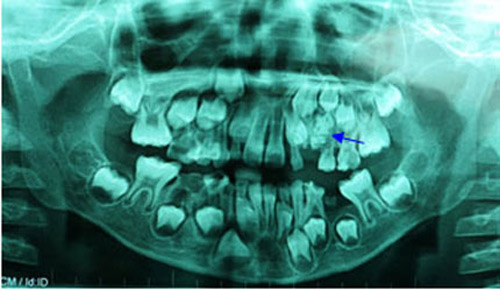

7 tuổi có 76 chiếc răng

Một bé trai 7 tuổi ở TP.HCM có tới 76 chiếc răng. Trong đó, 54 chiếc răng nhỏ li ti mọc trong khối u ở xương hàm còn 22 chiếc răng đã mọc trong miệng.

Các bác sỹ tại Khoa Răng Hàm Mặt BV Nhi Đồng 1 đã phải phẫu thuật để loại bỏ khối u răng cùng với răng nanh sữa mọc kẹt để giúp cho các răng vĩnh viễn mọc lên sau này được bình thường.

Hình chụp X-quang của bé trai có 76 chiếc răng